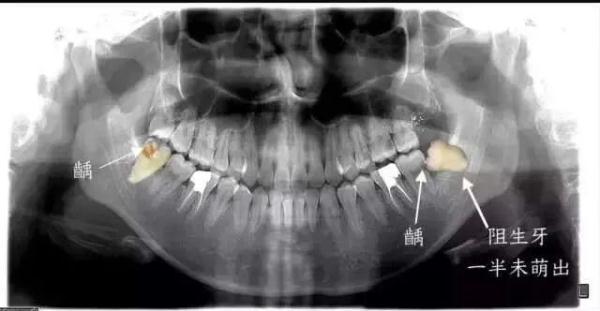

长歪的智齿非常不容易清洁,食物常常会残留,有的就会导致智齿及周围组织疼痛;

更严重的是,还会导致智齿前方的磨牙出现蛀牙,进一步则出现牙痛;

最严重的、也非常常见的状况,智齿要拔掉先不说,连同智齿前方的第二磨牙都出现不可挽救的龋坏,只能一起拔掉。

▲ 智齿前方的牙齿已经出现了蛀洞,即龋病

医生同时表示,健康的智齿可以不拔,还有一些智齿深深埋在骨头里,而且完全没有萌出到口腔的迹象,那么也可以先不拔。但是要保持观察,一有动静,还是要防范!